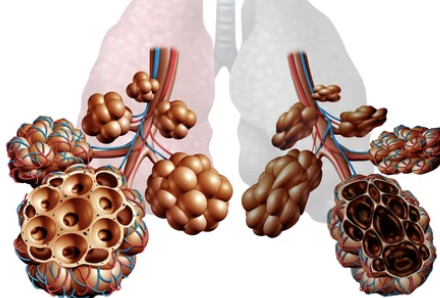

COPD란 무엇인가? — 한 번 손상된 폐는 스스로 회복되지 않는다

COPD(Chronic Obstructive Pulmonary Disease)는 말 그대로 폐가 만성적으로 좁아져 공기가 잘 드나들지 못하는 상태입니다. 폐포가 망가지고 기도가 좁아지면서 산소 교환이 떨어지고, 결국 숨이 차는 증상이 지속적으로 나타납니다.

- 비가역적(한번 손상되면 자연 회복 어려움)

- 천식과 달리 기관지 확장제 사용해도 완전 호전 어려움

- 담배 연기·미세먼지 등 장기간 노출이 주요 원인

- 대표적인 고령층 만성질환

초기에는 가벼운 기침으로 시작하지만, 진행되면 일상생활까지 제한할 만큼 증상이 심해질 수 있어 조기 인지가 중요합니다.